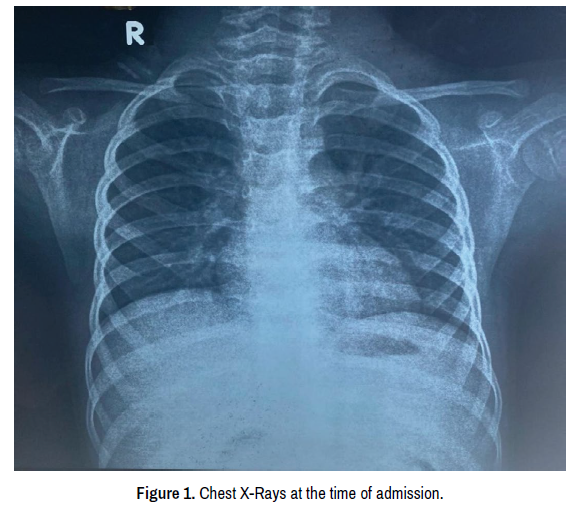

During the course of hospitalization over the next 2 weeks, the patient developed high-grade fever (documented up to 105’F), with a progressive increase in the size and the number of lymph nodes (maximum diameter of 2 x 2cm). On examination, he was febrile and tachycardia (HR-160/ min) was present. However, the BP was within the 50th and 95th centile (92/60mmHg), pulses palpable, and peripheries were warm. There was severe pallor and swelling, pain, and increased temperature of BL ankle and knee joints. There were multiple petechiae in B/L lower limbs. He also developed hepatosplenomegaly (Liver 3 cm BCM and spleen 5 cm BCM). Nosocomial infections were ruled out by sending a blood and urine culture and testing for malaria, dengue, and leptospirosis. All the reports were negative. A CBC was sent which was suggestive of pancytopenia. Repeat LFT was s/o elevated SGOT/SGPT, and inflammatory markers were raised. There was clinical and laboratory suspicion for systemic onset juvenile idiopathic arthritis with macrophage activation syndrome (Figure 1).

Figure 1. Chest X-Rays at the time of admission.

Investigation

Initial tests revealed hemoglobin of 8.1g/dl, TLC of 15200cells/mm3 (N76L20E2M1), and a platelet count of 4.47lacs/mm3 which later decreased to 5g/dl, 3639cells/mm3 (N55L40E1M1), and 40,000/mm3 respectively. At presentation, serum urea was 17.3mg/dL and serum creatinine 0.56mg/ dL, C-reactive protein (CRP) 79.73mg/dL, erythrocyte sedimentation rate (ESR) 100mm in 1st hour initially which reduced to 30mm during the course of hospitalization. Also, at two weeks of hospitalization, fibrinogen levels of 199mg/dL, ferritin levels of 100,000mg/dL, and triglyceride levels of 287.2mg/ dL were measured in serum. The Liver function test showed SGOT of 233.8IU/L and SGPT of 61IU/L and S.LDH of 2877IU/L. The initial chest X-ray was normal (Figure 1); however, a repeat chest X-ray showed the presence of BL pleural effusion (Figure 2). Clear pleural fluid was tapped, and routine microscopy showed a transudative picture and the culture was sterile. The patient was also investigated for tuberculosis as per the NTEP (National Tuberculosis Elimination Programme) protocol, the chest X-ray was not suggestive of TB; negative results for Acid fast bacilli and CBNAAT were obtained from a gastric aspirate [7]. The excisional biopsy of the enlarged cervical lymph nodes was done to rule out lymphoma, which was suggestive of reactive lymphadenitis. S.ANA and Rheumatoid factor were negative. Bone marrow aspiration and biopsy done initially were suggestive of normal haematopoiesis. During the course of hospitalization, the patient developed a high-grade fever; thus, blood and urine cultures were sent to rule out nosocomial infection; however, both cultures were negative. IgM dengue, IgM scrub typhus, and IgM Leptospira were also negative. EBV DNA RTPCR was also done which was negative. IgM CMV, CMV DNA, and Parvo B19 DNA RTPCR were sent which were negative. 2D ECHO was done to rule out infective endocarditis and it turned out normal. Repeat bone marrow was suggestive of hemophagocytosis. The PRINTO criteria for SOJIA with MAS were fulfilled. Prior to discharge, repeat inflammatory markers were assayed and ferritin was lowered to 6928.3mg/dL, triglycerides were 186 mg/dL, CRP was 40mg/L, and the ESR was 50mm in the 1st hour (Table 1).